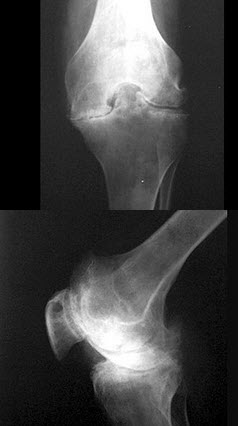

285、单项选择题

男,30岁,右膝关节酸胀,疼痛不适5个月,X线检查如图所示,最可能的诊断是()

A.骨巨细胞瘤

B.骨囊肿

C.骨血管瘤

D.动脉瘤样骨囊肿

E.以上均不正确

点击查看答案